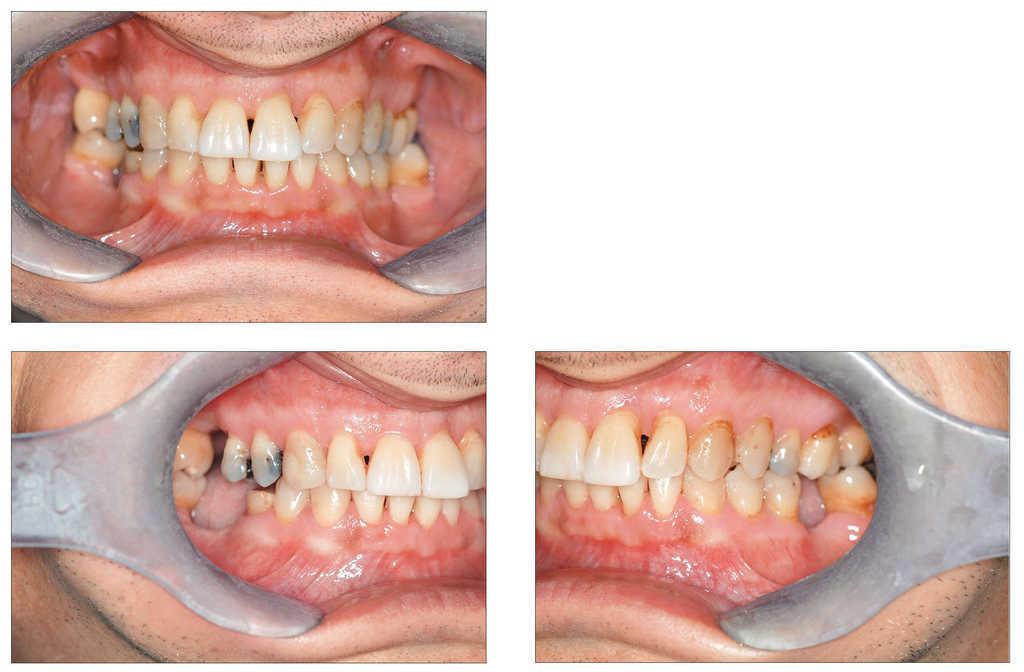

A pesar de que el odontólogo de cabecera había realizado un raspaje a cielo cerrado hacía menos de 2 meses, se observó un absceso periodontal subagudo supurado en los dientes 31 y 21 con destrucción periodontal grave. El diente 31 reaccionó positivamente a la prueba de sensibilidad al frío a pesar de mostrar una pérdida de inserción avanzada en mesial hasta el ápice (profundidad de sondaje [PPD] 11 mm en mesial). El aspecto de la encía correspondía al de un fumador importante: a pesar del grado de destrucción periodontal, la encía mostró un color rosa pálido con una queratinización intensa. El sangrado al sondaje (BOP) estaba muy disminuido como resultado del gran consumo de tabaco y, por lo tanto, se pasó por alto como signo de alerta precoz. Como consecuencia de la elongación secundaria a la destrucción periodontal el diente 21 (PPD 5278) mostraba un traumatismo oclusal. El paciente experimentó una mayor disminución de la dimensión vertical debido a la mesioversión del diente 37. La higiene bucal individual dejó entrever evidentes posibilidades de mejora. En las radiografías se observó una pérdida de inserción horizontal generalizada y vertical localizada (figs. 1 y 2).

Figura 1. Radiografías preoperatorias del 29/8/2006 facilitadas por el odontólogo remitente.

Figura 2. Situación clínica antes del tratamiento inicial.